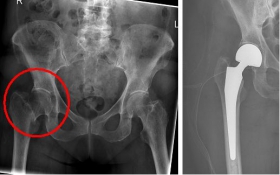

Oberschenkel 4

Picture: In this case, there was already a wear of the hip joint and the affected patient was relatively young, so that a cement-free total endoprosthesis (TEP) of the hip was selected for the treatment of the femoral neck fracture. Here, in addition to the femoral head, the acetabular cup was replaced by an implant.

In older age and with stronger displacement of the fracture can be done by a duo-head prosthesis. Here only the femoral head is replaced, the hip socket is preserved. In case of simultaneous hip arthrosis, a total endoprosthesis (hip replacement) with replacement of the acetabular cup can be used.